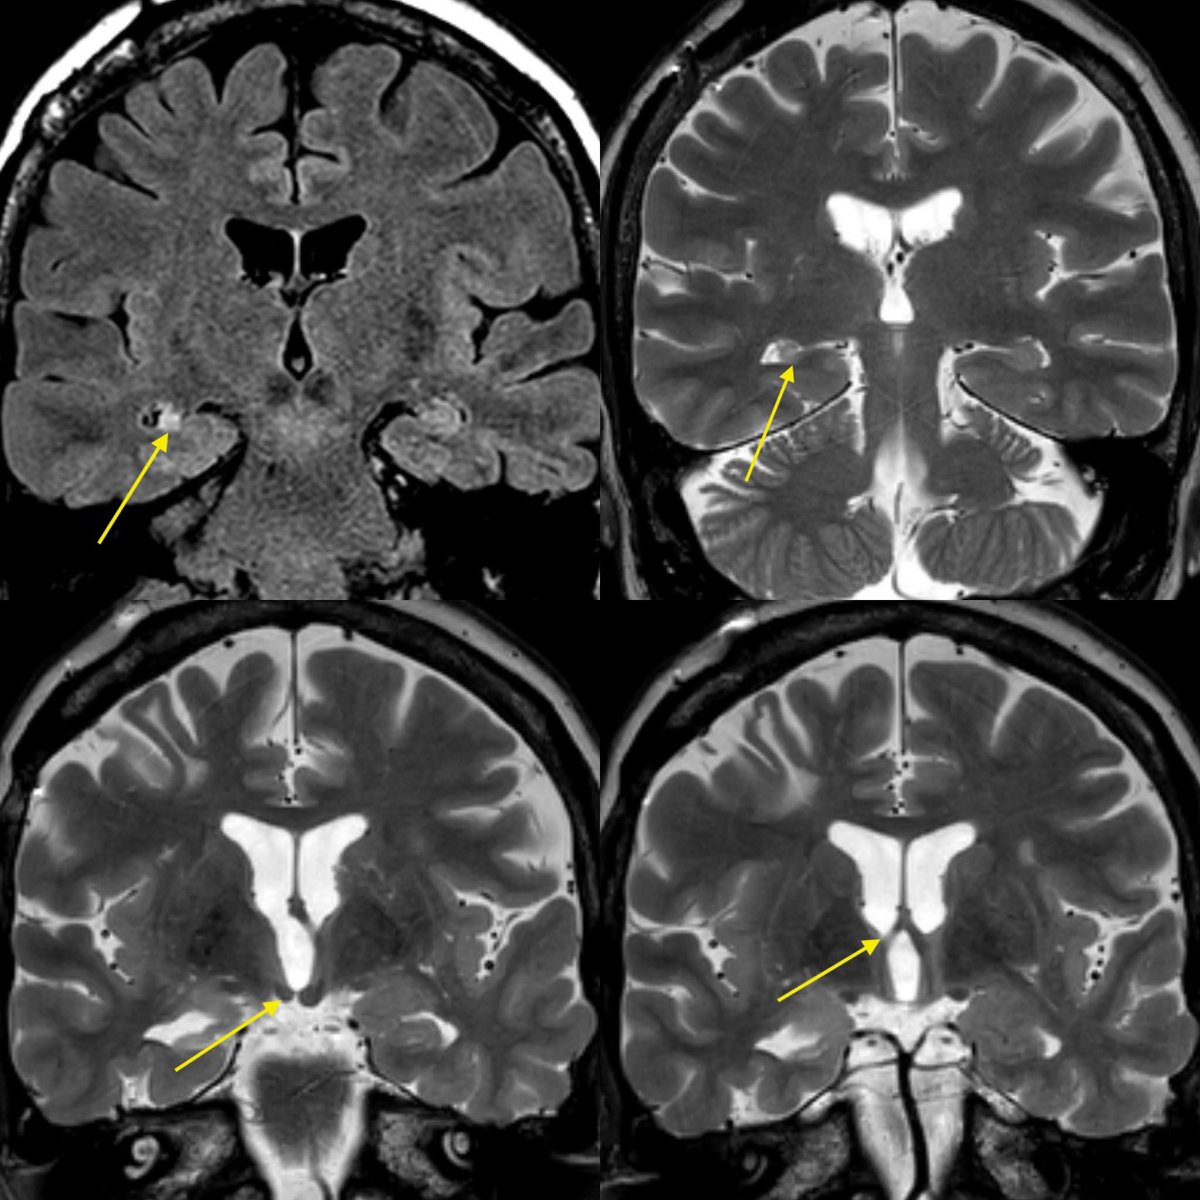

Wondering what are impacted wisdom teeth? Learn why these trapped third molars cause pain, swelling, and infection. Discover the common symptoms, oral health risks, and effective surgical treatment options available to prevent further dental complications. Get the expert insights you need to understand when it is time for a professional wisdom tooth extraction and restore your dental health today.